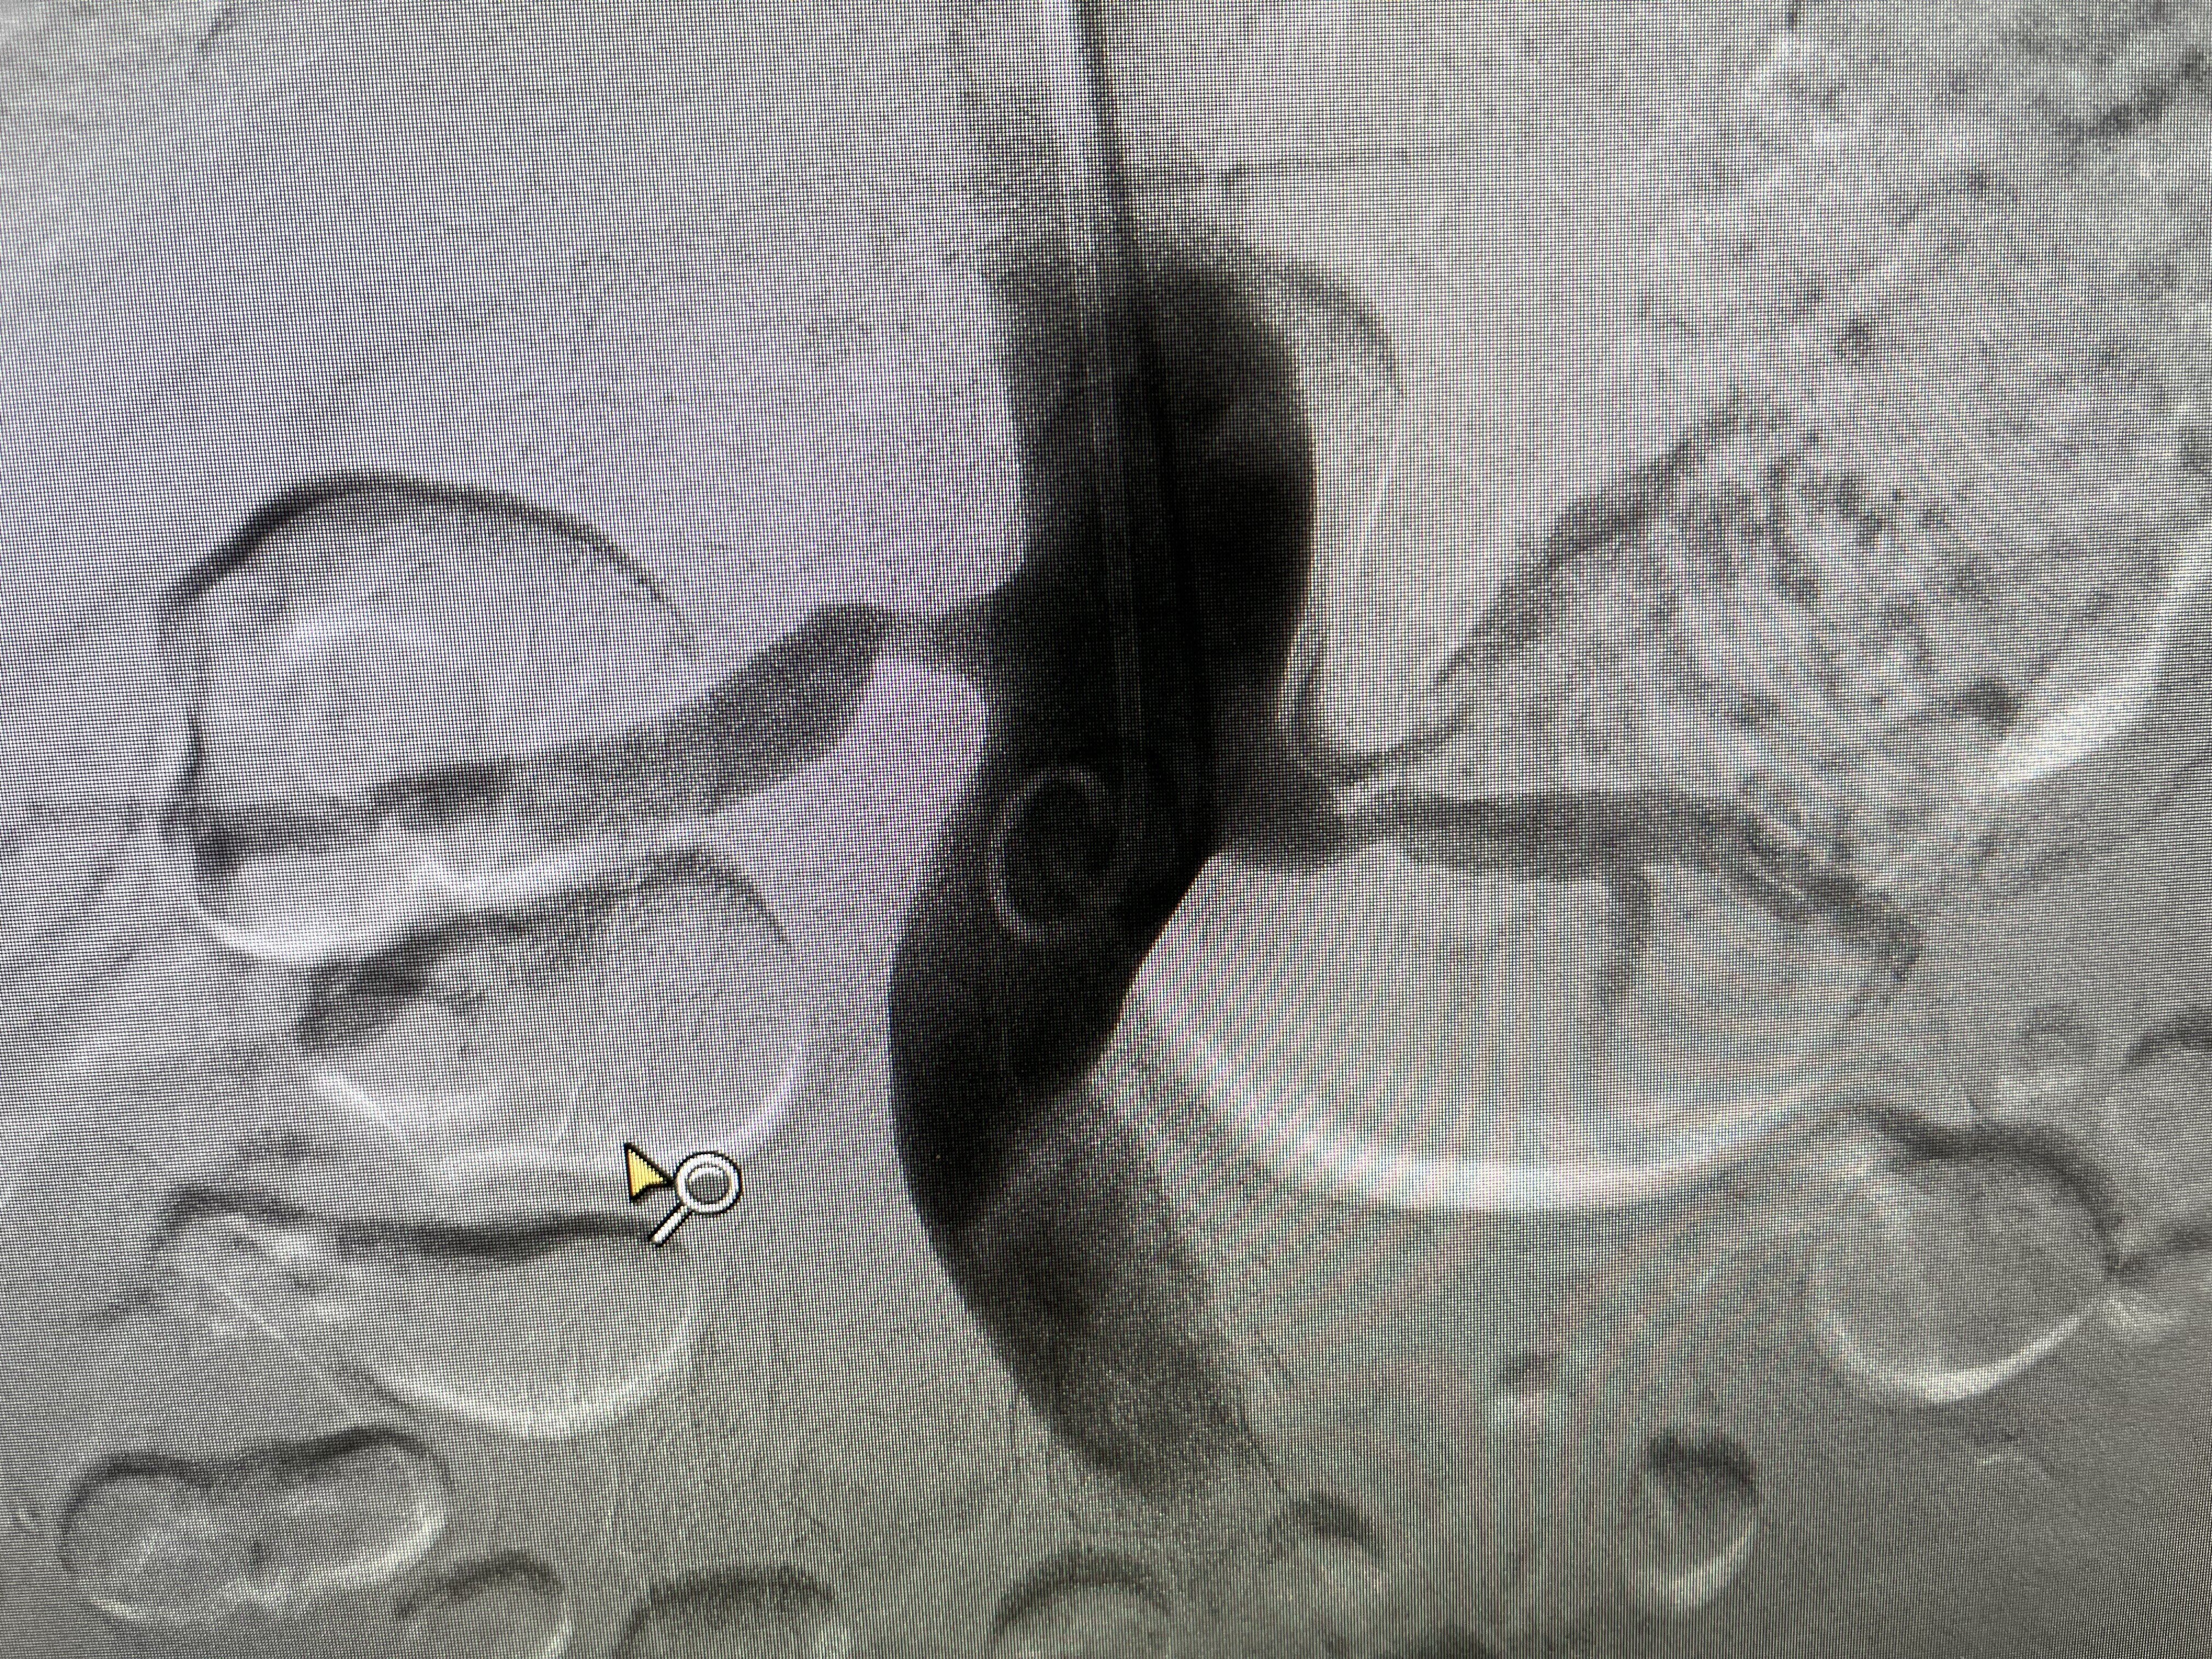

血液透析血管通路是透析患者的生命線,隨著人口老齡化、糖尿病腎病患者增加,以及透析時(shí)間的延長,越來越多的患者開始使用人工血管內(nèi)瘺透析。人工血管動(dòng)靜脈內(nèi)瘺較自體動(dòng)靜脈內(nèi)瘺穿刺更復(fù)雜,現(xiàn)將部分穿刺、護(hù)理要點(diǎn)列舉如下,今后我們還會陸續(xù)發(fā)布相關(guān)的系列專科文章,希望為大家提供一些幫助。1、穿刺時(shí)機(jī):因手術(shù)創(chuàng)面大,皮下組織受損多,術(shù)后肢體均有不同程度的腫脹。雖然文獻(xiàn)報(bào)道術(shù)后2-4周可以穿刺透析,但我們觀察到一般術(shù)后6-8周腫脹才可以完全消退,新的內(nèi)、外膜逐漸形成,人工血管輪廓變得清晰。過早使用易使移植血管壓縮,吻合口狹窄,出血,感染及血栓形成,因此一般選擇術(shù)后6-8周穿刺人造血管為宜。如果人造血管通路失功能,經(jīng)手術(shù)干預(yù)再通后,傷口無滲血、腫脹、術(shù)后第一天即可使用。2、穿刺部位:動(dòng)、靜脈穿刺點(diǎn)距離吻合口>3cm,兩點(diǎn)間距>5cm.不宜在血管轉(zhuǎn)彎、弧形及皺褶部位穿刺;采取階梯式或螺旋式不定點(diǎn)穿刺,每次穿刺部位距上次進(jìn)針0.6-1.2cm。3、穿刺方向:對穿刺范圍較短的人工血管,動(dòng)脈穿刺為逆血流方向,可減少再循環(huán)率。對穿刺范圍較長的人工血管,動(dòng)脈穿刺針可為順或逆血流方向,順血流方向穿刺使血流對拔針后可能存在的活瓣影響小,有利于血管針眼的愈合,靜脈穿刺針為順血流方向。4、穿刺方法:穿刺前摸清血管的走形、深淺,穿刺不需用止血帶。嚴(yán)格執(zhí)行無菌操作原則,以穿刺點(diǎn)為中心由內(nèi)向外螺旋式消毒穿刺區(qū)域皮膚,消毒范圍直徑大于10cm,消毒兩遍。針尖斜面向上,以40°-45°角進(jìn)針,刺入皮膚有頓感時(shí)觸及人工血管,進(jìn)入人工血管后可感有落空感,見回血后將穿刺針與皮膚的角度減到20°—30°,繼續(xù)血管內(nèi)推進(jìn)至針身全部送入,然后將針旋轉(zhuǎn)180°,使針斜面向下,固定穿刺針至恰當(dāng)舒適位,嚴(yán)防穿刺針異位或脫出。對于人工血管植入較深或肥胖的患者,當(dāng)不能清晰觸摸到血管邊緣時(shí),可將人工血管捏起,使其高于皮膚,有利于提高穿刺的成功率。應(yīng)采取階梯式或螺旋式進(jìn)針方法,使穿刺不固定于整個(gè)血管通路的任何區(qū)域。5、拔針及止血:拔針時(shí)確認(rèn)針尖斜面向下,用無菌棉球壓迫穿刺點(diǎn),拔針后指壓止血15-20min,壓迫點(diǎn)在人工血管進(jìn)針處,注意不要在拔針過程中加壓,要在拔針后加壓,以免穿刺針斜面切割血管。壓迫時(shí)間不宜過長,力量適中,以能觸及近心端人工血管震顫或聽診可聞及血管雜音為宜。壓力過大易致血流阻斷,壓力過小易出血,壓迫時(shí)間過長易導(dǎo)致血栓形成。 圖1 動(dòng)、靜脈穿刺點(diǎn)距離吻合口>3cm,不宜在血管轉(zhuǎn)彎、弧形及皺褶部位穿刺 6、日常護(hù)理:透析治療中觀察血壓變化,若血壓低于100/60mmHg要及時(shí)處理,防止長時(shí)間的低血壓致血流緩慢使血栓形成。如果發(fā)現(xiàn)患者內(nèi)瘺肢體腫脹或者靜脈回流壓力增高應(yīng)警惕瘺血管近心端狹窄,及時(shí)告知醫(yī)生。 圖2 1、1,2、2分別代表第1次穿刺點(diǎn),第2次穿刺點(diǎn)